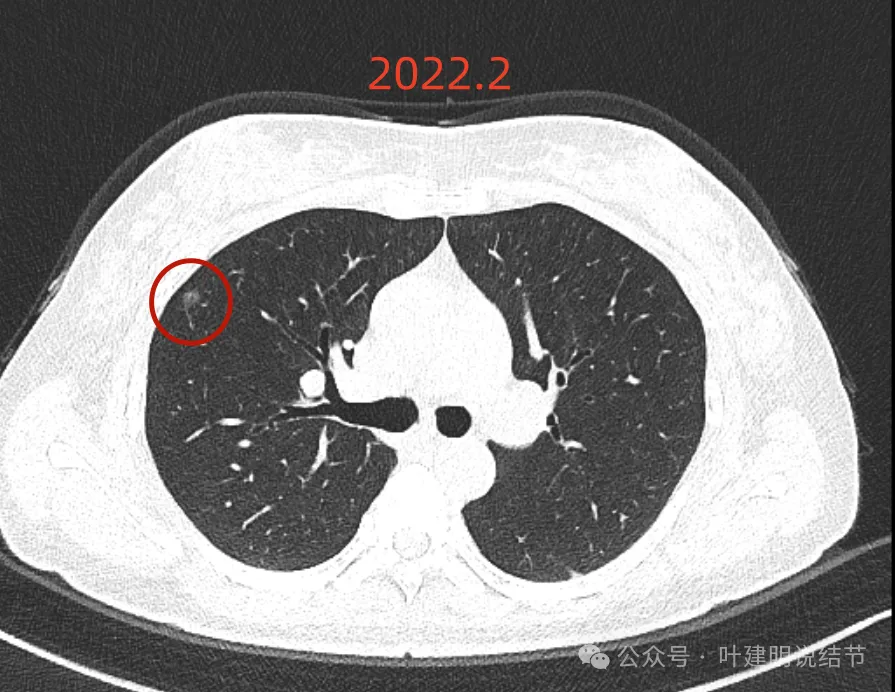

我们先来看2022年2月时病灶最明显部位的截图:

这是A医院主张手术时的影像:

右上主病灶,磨玻璃密度,灶内不是很均匀,似见小空泡征,有微小血管走向病灶并进入,但说不上明显异常增粗,整体轮廓与边界清,考虑是肿瘤范畴的结节。

右中叶病灶也是淡的磨玻璃密度,瘤肺边界稍显不清,密度不是太均匀。大概是肺泡上皮增生或不典型增生之类的可能性,也可能慢性炎伴少许纤维增生。

左上叶磨玻璃结节,有微小血管进入,整体轮廓较清,瘤肺边界不如右上主病灶清楚,但持续存在的话,基本上也是肿瘤范畴的。